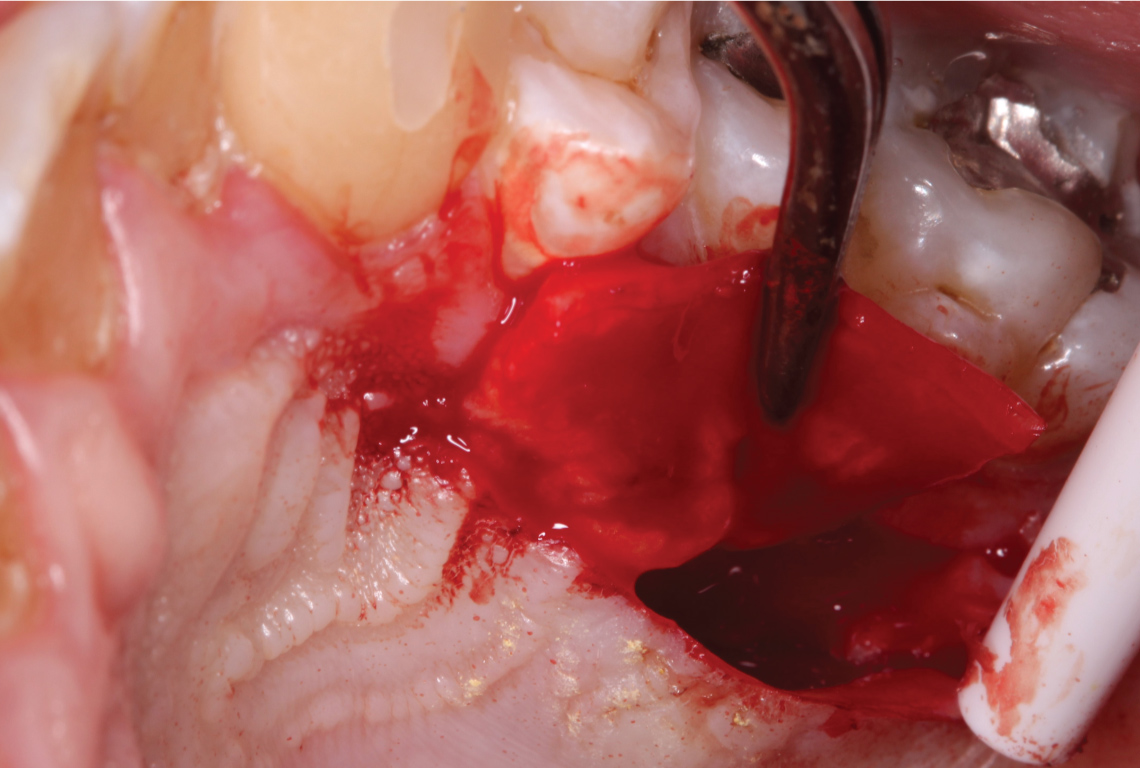

Findings, treatment options and risks for sub epithelial connective graft on the mandibular lingual region were discussed with patient and consent obtained for the same. Prior to surgery, patient was asked to rinse with 0.2% chlorhexidine digluconate solution. After administering local anesthesia (2% lidocaine with 1/100,000 epi), the exposed root surface was debrided with curettes and piezo tip. Intrasulcular incisions were made on lingual of #22-24 with #15 blade. Instruments included in the Pat Allen soft tissue kit were used to undermine the lingual soft tissue, careful to not perforate the lingual mucosa. The dissection was extended apically beyond mucogingival junction and laterally extending beyond #22-24 sites without severing the intact interdental papilla. Tension free mobility of the soft tissue complex was achieved by carefully reflecting apically, mesially and distally to form a sub-periosteal tunnel or a pouch (Figure 2). Any muscle fibers still present were carefully released. Due to access difficulty, care was taken to prevent any mucosal perforations and release of the interdental papillae. The gingival margin of the recession was passively approximated covering most of the exposed root surface. The exposed root of #23 was burnished with tetracycline and irrigated with saline.

Figure 2: Tension free pouch created to receive the SCTG. View Figure 2

A sub-epithelial connective tissue graft (SCTG) was harvested using double parallel incisions as described by Harris on palate which was approximately 15 mm in length [9] (Figure 3). The donor site was closed by cross mattress stabilizing sutures using 4.0 chromic gut. Stabilizing sling suture was utilized to stabilize the connective tissue graft at the recipient site. The graft was tunneled laterally underneath adjacent papilla. 5.0 chromic sutures were used to sling the graft to #23 (Figure 4). After the SCTG was fixed by the sling sutures to the lingual exposed root surface at the CEJ, lateral margin of recession was approximated to cover the graft and closed with 6.0 polypropylene sutures. Simple interrupted loop sutures were utilized to close margins (Figure 5 and Figure 6). Only a minimal amount of connective tissue graft was exposed after approximating the lateral margins. Hemostasis was achieved with compression by a gauze.

Figure 3: SCTG harvested from the palate with a double incision technique. View Figure 3